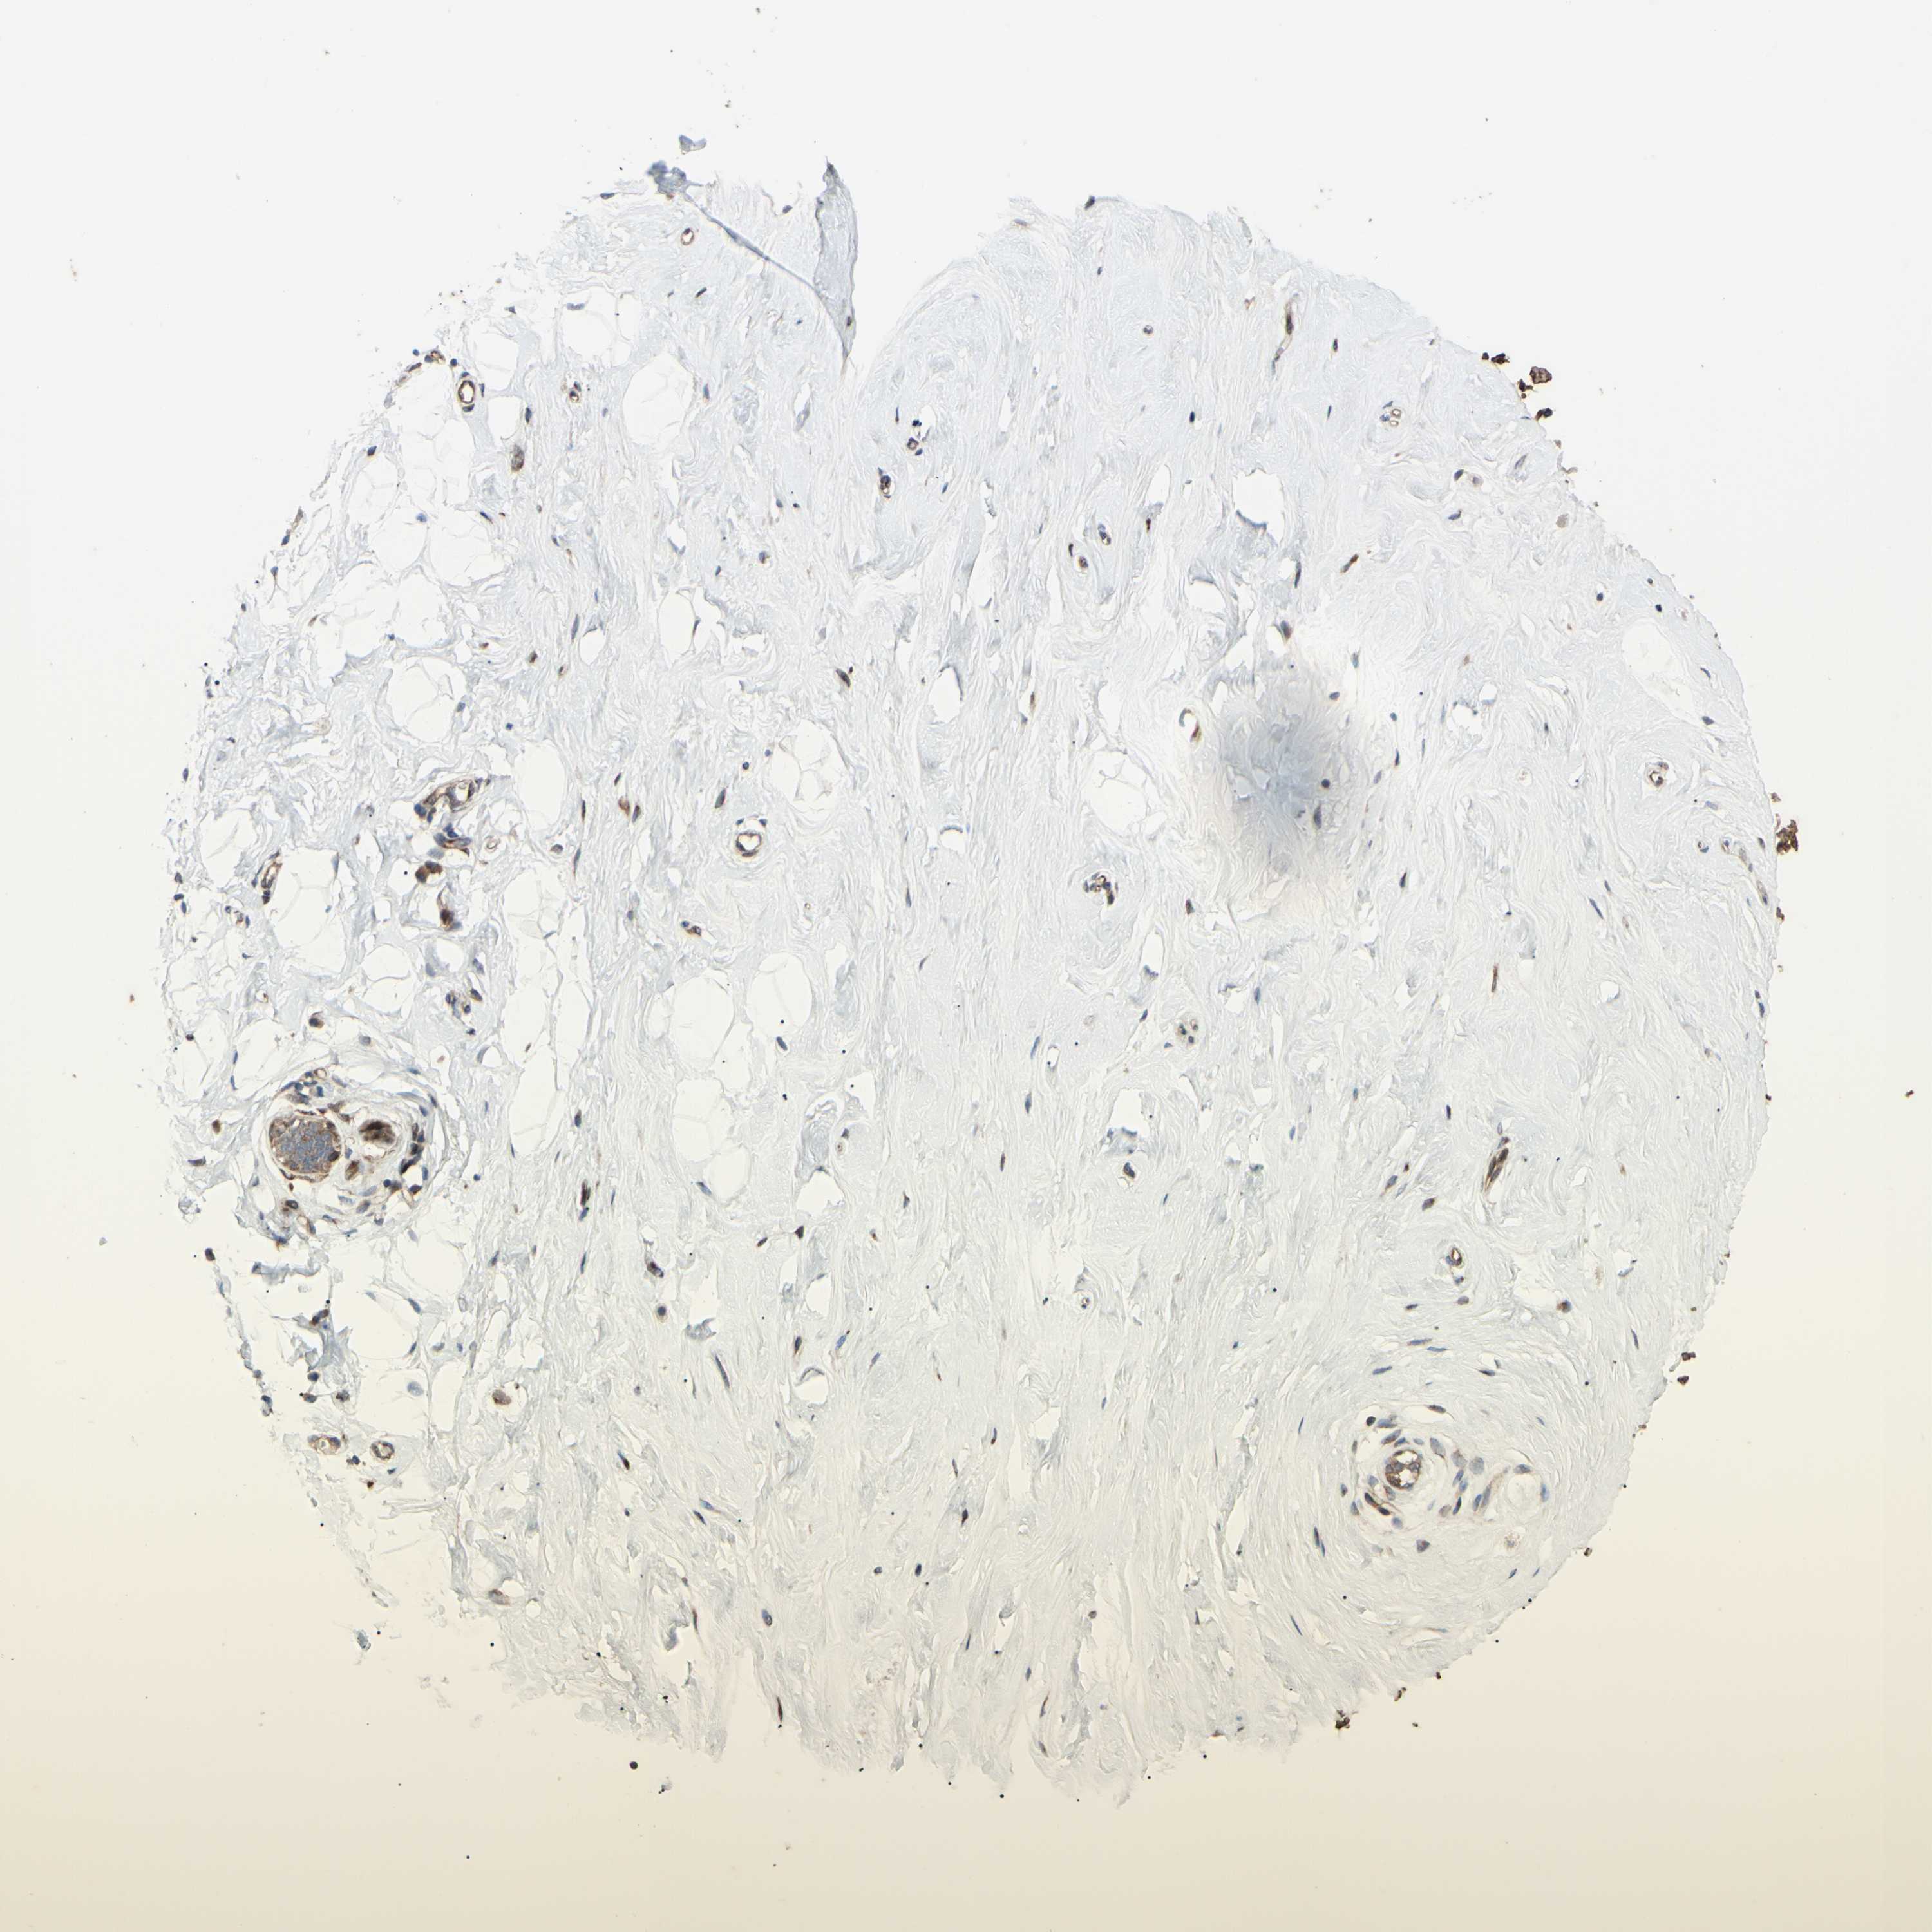

BREAST - Antibody stainingi

Antibody staining in the annotated cell types in the current human tissue is reported as not detected, low, medium, or high, based on conventional immunohistochemistry profiling in selected tissues. This score is based on the combination of the staining intensity and fraction of stained cells.

Each image is clickable and will lead to virtual microscopy that enables deeper exploration of all samples and also displays staining intensity scores, fraction scores and subcellular localization as well as patient and tissue information for each sample.

Antibody HPA002859Antibody CAB011655

Adipocytes -Not detected

Glandular cells Not detectedLow

Myoepithelial cells Not detectedLow